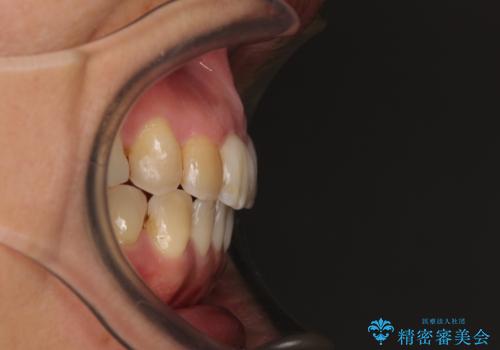

前歯の後戻り インビザラインでの再矯正治療

- かつて抜歯矯正を行ったものの、後戻りをしてしまったとのことで来院された患者様です。

上顎前歯が前突し、隣の歯が裏側に移動してきている状態でした。

飲み込みの状態を確認したところ、舌の突出癖が認められたため、それによる後戻りの可能性が高いと考え、舌のトレーニングを指導しました。

舌のトレーニングをしっかりと行ってくださり、10ヶ月で希望通りの歯列となりました。

日頃から飲まれる飲み物の影響で着色しやすいため、来院の度に着色除去のクリーニングも行っていました。